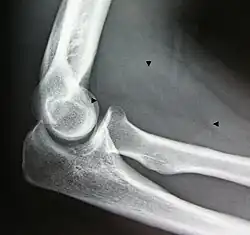

X-ray of a lipoma -

Bone formation may be seen in both lipomas[26] and liposarcomas (a well-differentiated one pictured).